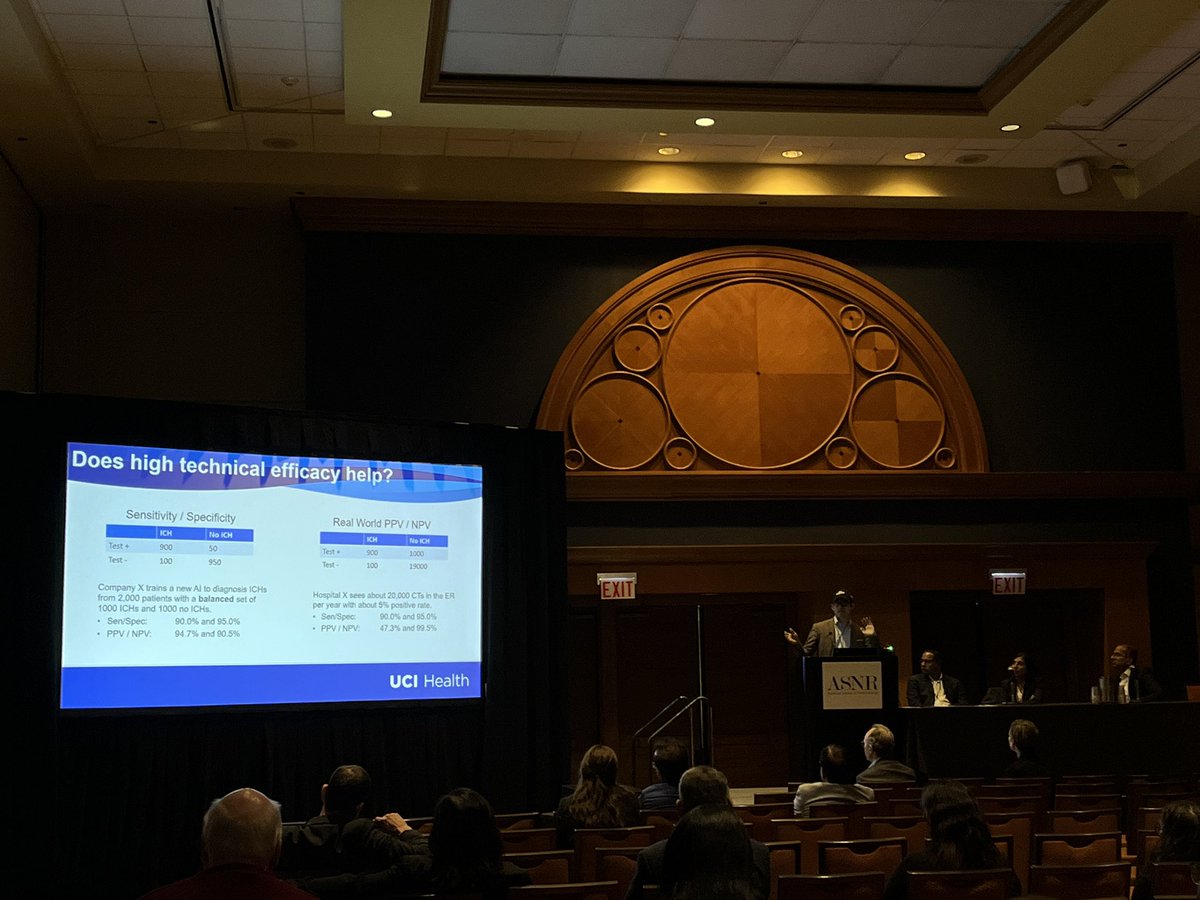

Intriguing talk from my former #cofellow @DanChow01… could #imagingai actually lead to MORE #burnout??? 🤔🤔🤔 #asnr23 #ebm

Intriguing talk from my former #cofellow @DanChow01… could #imagingai actually lead to MORE #burnout??? 🤔🤔🤔 #asnr23 #ebm